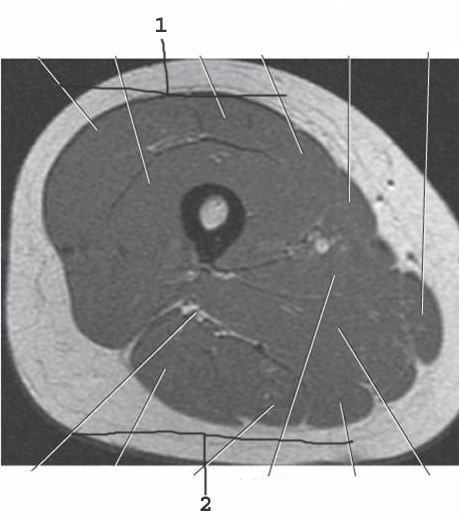

1

Aorta

2

Left common iliac artery

3

Left internal iliac artery

4

left external iliac artery

5

left femoral artery